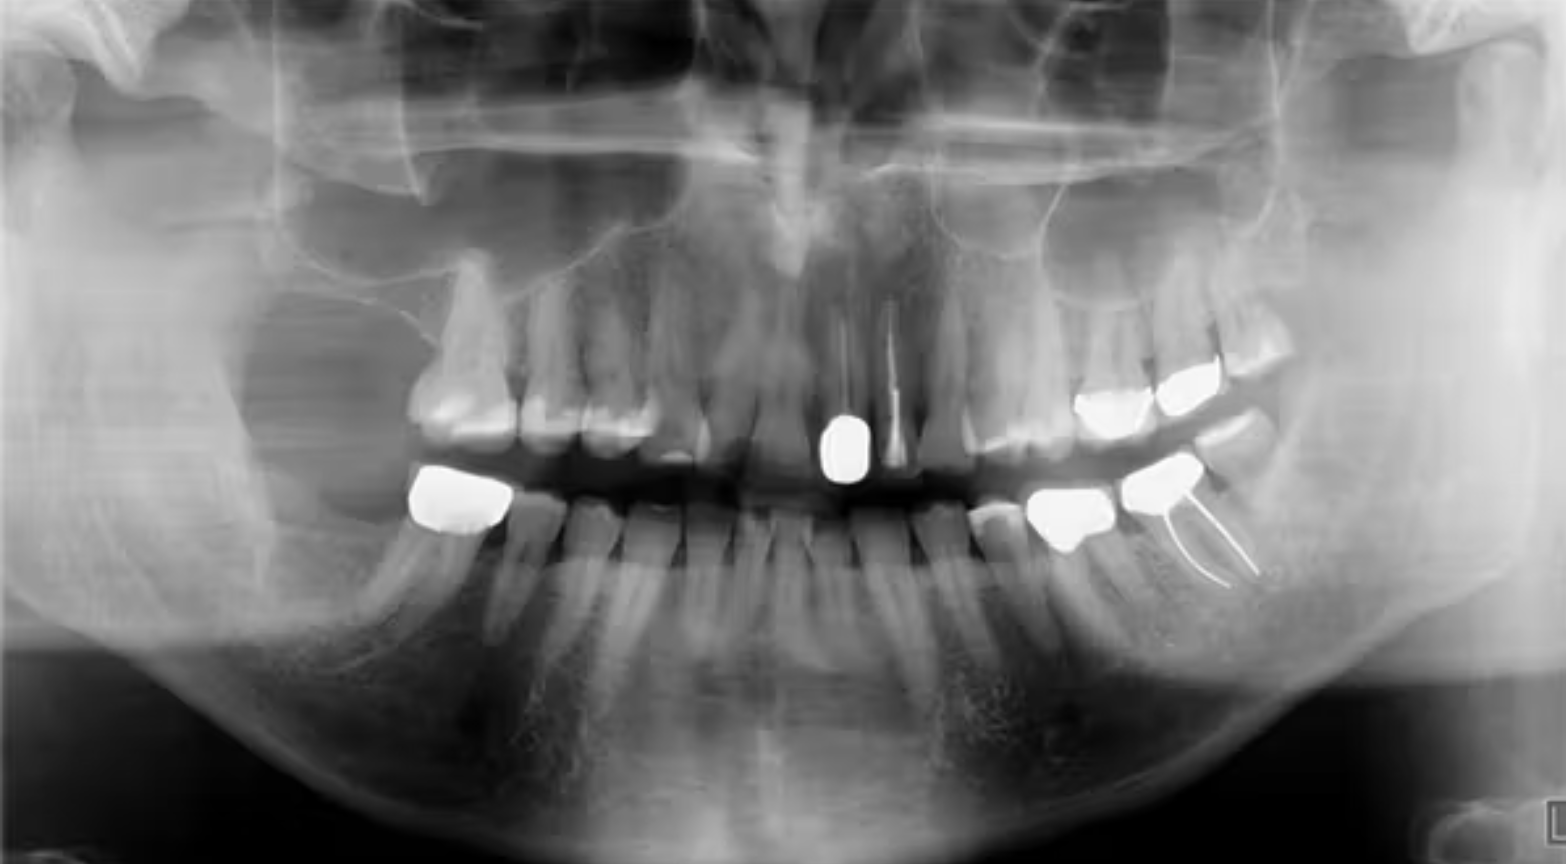

Khi chụp X-quang, bác sĩ có thể nhận thấy một hình dạng giống như ổ chân răng ở vùng đã nhổ, thường là nhiều năm sau khi bệnh nhân có than phiền (Hình 1 và 2). Đây được gọi là ổ chân răng sót lại (residual root socket). Đường viền của ổ chân răng vẫn mờ mờ nhìn thấy, và khi thăm khám phẫu thuật, vùng này có thể rỗng hoặc được lấp đầy bởi mô sẹo xơ đặc, mô hạt hoặc xương non chưa trưởng thành.

(Hình 1: Ổ chân răng sót lại, cho thấy đường viền chân răng cũ của răng hàm lớn – Nguồn: GS Jerry E. Bouquot, University of Texas, Houston.)

Ổ chân răng sót lại có thể được phát hiện trên X-quang, thường không phải là một vấn đề khẩn cấp trừ khi bệnh nhân có cảm giác khó chịu hoặc đau tại vùng đó. Từ những báo cáo đầu tiên về hiện tượng này, chúng ta đã hiểu rõ hơn về sức khỏe xương, cơ chế lành thương và quá trình phát triển – tiêu xương. Đặc biệt, phẫu thuật cấy ghép implant ngày nay đã rất phổ biến và thành công. Tuy nhiên, chưa có bằng chứng rõ ràng rằng việc đặt implant vào vùng có dấu hiệu ổ chân răng sót lại trên X-quang là chống chỉ định.

(Hình 2: Ổ chân răng sót lại ở hàm dưới bên trái – Nguồn: Dr. Jerry E. Bouquot.)